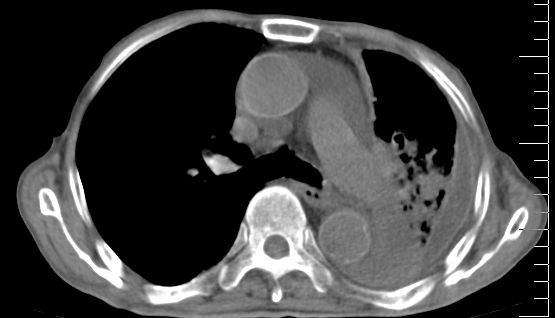

标题: CT10141:男、84岁,咳嗽、咯血1年。 [打印本页]

标题: CT10141:男、84岁,咳嗽、咯血1年。

1左侧胸腔积液并包裹2心包积液3左下肺癌?建议支纤镜检。

支持左侧中央型肺癌伴下叶肺不张\\纵隔淋巴结转移.左侧包裹性胸腔积液\\心包积液.左侧少量胸腔积液..慢性支气管炎伴部分间质纤维化.

咯血病史较长,左肺下叶实变,体积未明显缩小,隐约可见血管影及坏死阴影,双肺门及纵隔淋巴结增大,心包增厚积液,纵隔右移位,单侧胸腔积液,首先考虑:大叶型肺泡癌伴纵隔心包转移。